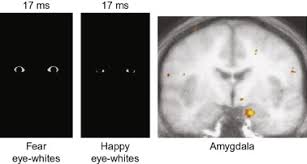

This activity reviews the evaluation and treatment of KBS and highlights. IN 1937 Klüver and Bucy 1 described a striking behavioral syndrome in rhesus monkeys after bilateral temporal lobe ablations. Kluver-Bucy syndrome KBS is a rare neuropsychiatric disorder due to lesions affecting bilateral temporal lobes especially the hippocampus and amygdala.

Klüver-Bucy syndrome is a rare behavioral impairment that is associated with damage to both of the anterior temporal lobes of the brain.